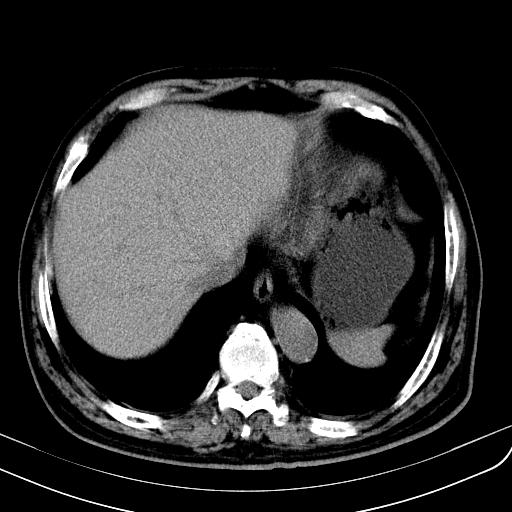

胃底靠近胃大弯处可见一圆形软组织影,直径为3.45cm,ct值约为30.1hu